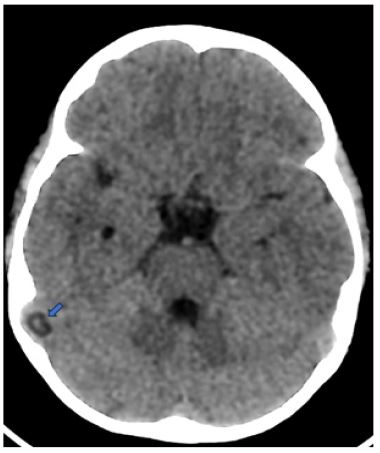

We report the case of a 5-year-old child who presented to the emergency room with febrile behavioral disturbances, including sudden-onset seizures, and visual hallucinations. Brain CT revealed a well-defined, round lesion of cerebrospinal fluid density protruding into the lumen of the right sigmoid sinus, causing a nodular filling defect. Based on its characteristic location and imaging features, the lesion was diagnosed as a giant Pacchionian granulation (Figure 1).

Figure 1: Non-enhanced axial CT shows well-defined hypoattenuating areas in the right sigmoid sinus (arrow).